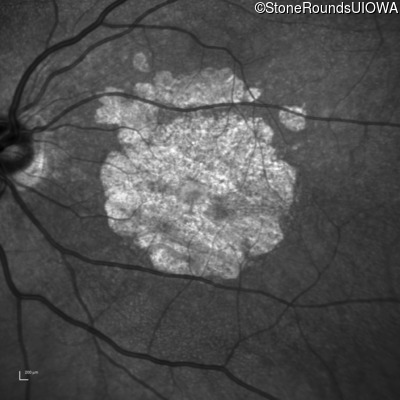

Blue Autofluorescence - Right - 10/300

Exemplar